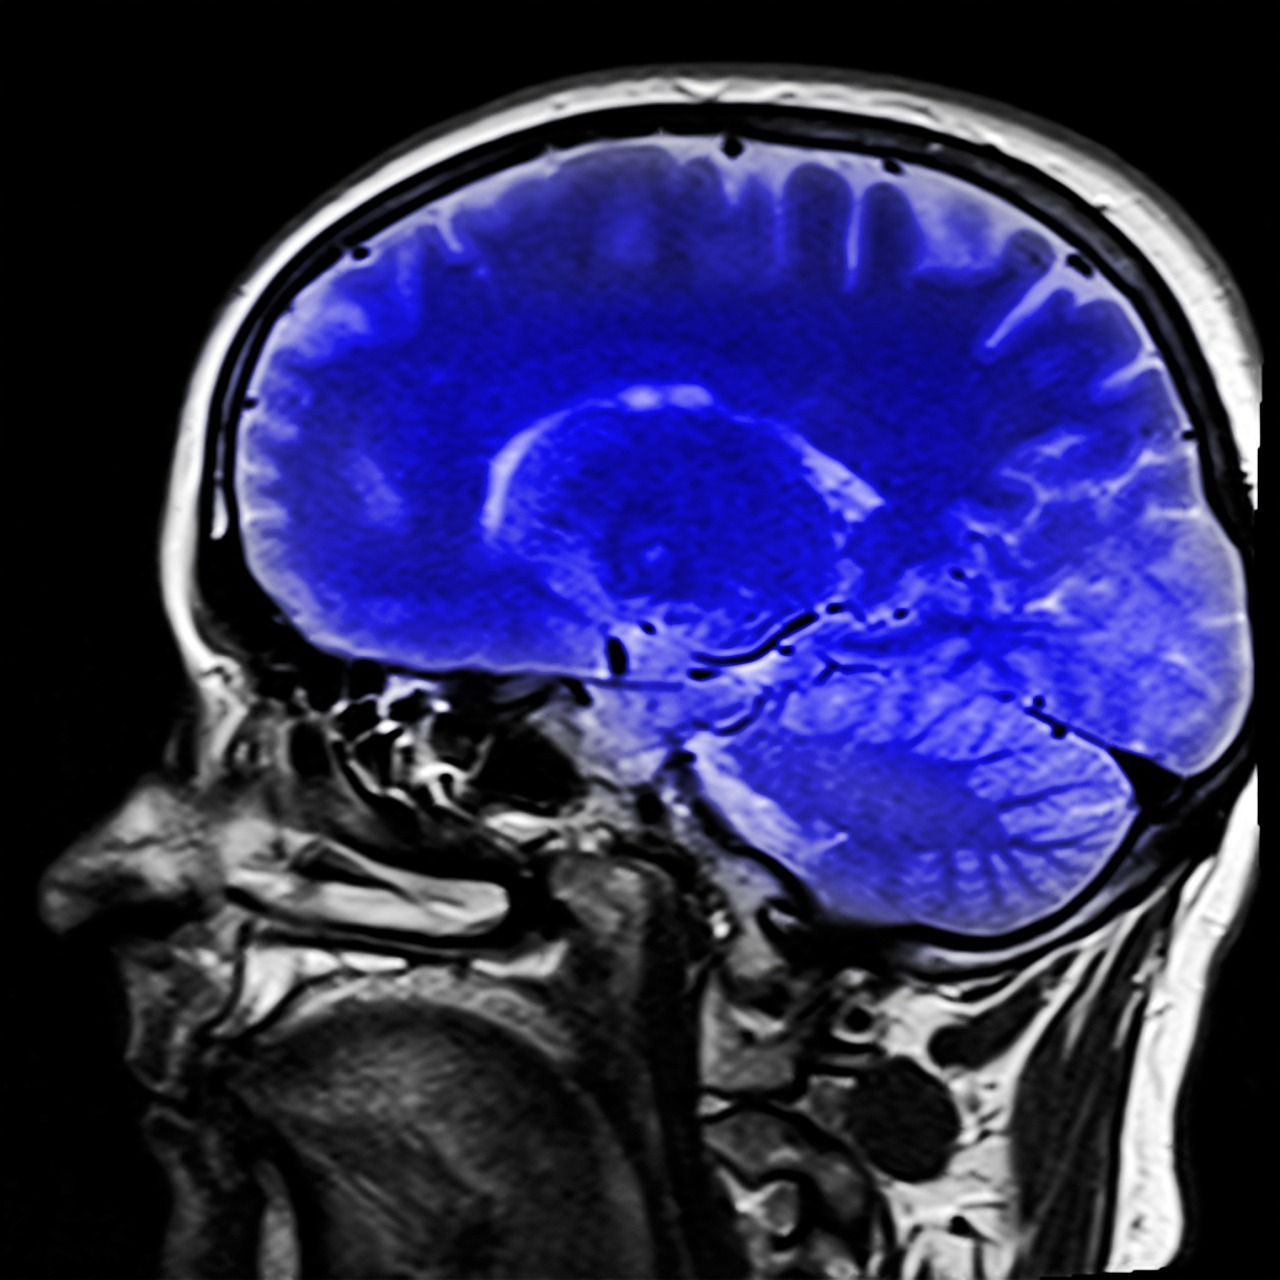

¿Cómo afecta realmente el consumo de cannabis en el cerebro?

Como todo, no hay una respuesta sencilla, ya que, si bien es cierto que el uso del cannabis para fines medicinales ha demostrado ser un gran aliado en enfermedades neurológicas, también se ha comprobado que su consumo crónico para fines no medicinales o “recreativos” dificulta al consumidor realizar ciertas tareas mentales mientras se encuentra bajo sus efectos.